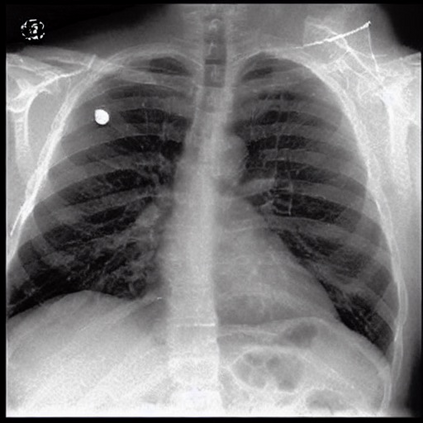

To address these issues, we propose a novel Adaptive patch-word Matching (AdaMatch) model to correlate chest X-ray (CXR) image regions with words in medical reports and apply it to CXR-report generation to provide explainability for the generation process. AdaMatch exploits the fine-grained relation between adaptive patches and words to provide explanations of specific image regions with corresponding words. To capture the abnormal regions of varying sizes and positions, we introduce the Adaptive Patch extraction (AdaPatch) module to acquire the adaptive patches for these regions adaptively. In order to provide explicit explainability for CXR-report generation task, we propose an AdaMatch-based bidirectional large language model for Cyclic CXR-report generation (AdaMatch-Cyclic). It employs the AdaMatch to obtain the keywords for CXR images and `keypatches' for medical reports as hints to guide CXR-report generation. Extensive experiments on two publicly available CXR datasets prove the effectiveness of our method and its superior performance to existing methods.